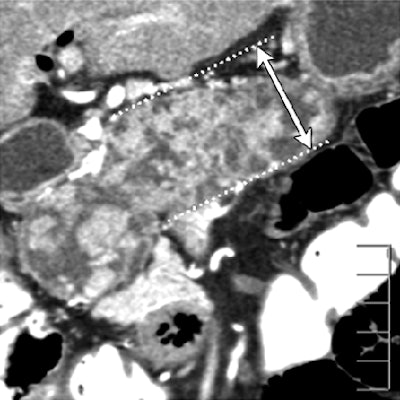

| Dilatation of main pancreatic duct (MPD) in intraductal papillary mucinous neoplasms of the pancreas (IPMN). Oblique coronal reformatted images were generated from pancreatic phase scanning, with 5-cm scale at lower right on each image. Above, adenoma; below, noninvasive carcinoma; bottom, invasive carcinoma. As the maximum diameter of the MPD (arrows indicate distance between dotted lines) increased by 3.8 mm (top), 21.4 mm (below), and 40.9 mm (bottom), the likelihood of malignancy of IPMN increased. Arrowhead on image below indicates protrusion of dilated MPD, showing water attenuation into the ampulla of Vater. Many mural nodules are seen in dilated MPD in invasive carcinoma on bottom image. |

The following findings showed significant differences among the three groups: maximum diameter of the main pancreatic duct (MPD), size (length of major axis) of the largest mural nodule in the MPD or in any associated cystic lesion, abnormal attenuating area in the surrounding parenchyma, calcification in the lesion, protrusion of the MPD into the ampulla of Vater, and bile duct dilatation, the authors reported.

"Of seven findings that were significant predictors of invasion in the univariate analysis, the following two findings remained significant in the multivariate analysis: presence of a mural nodule in the MPD of 6.3 mm or larger, and presence of an abnormal attenuating area in the surrounding parenchyma," the authors wrote.

When tumors meeting one or both of these criteria were identified as invasive, CT's sensitivity, specificity, and accuracy for detecting parenchymal invasion were 90%, 88%, and 89%, respectively.